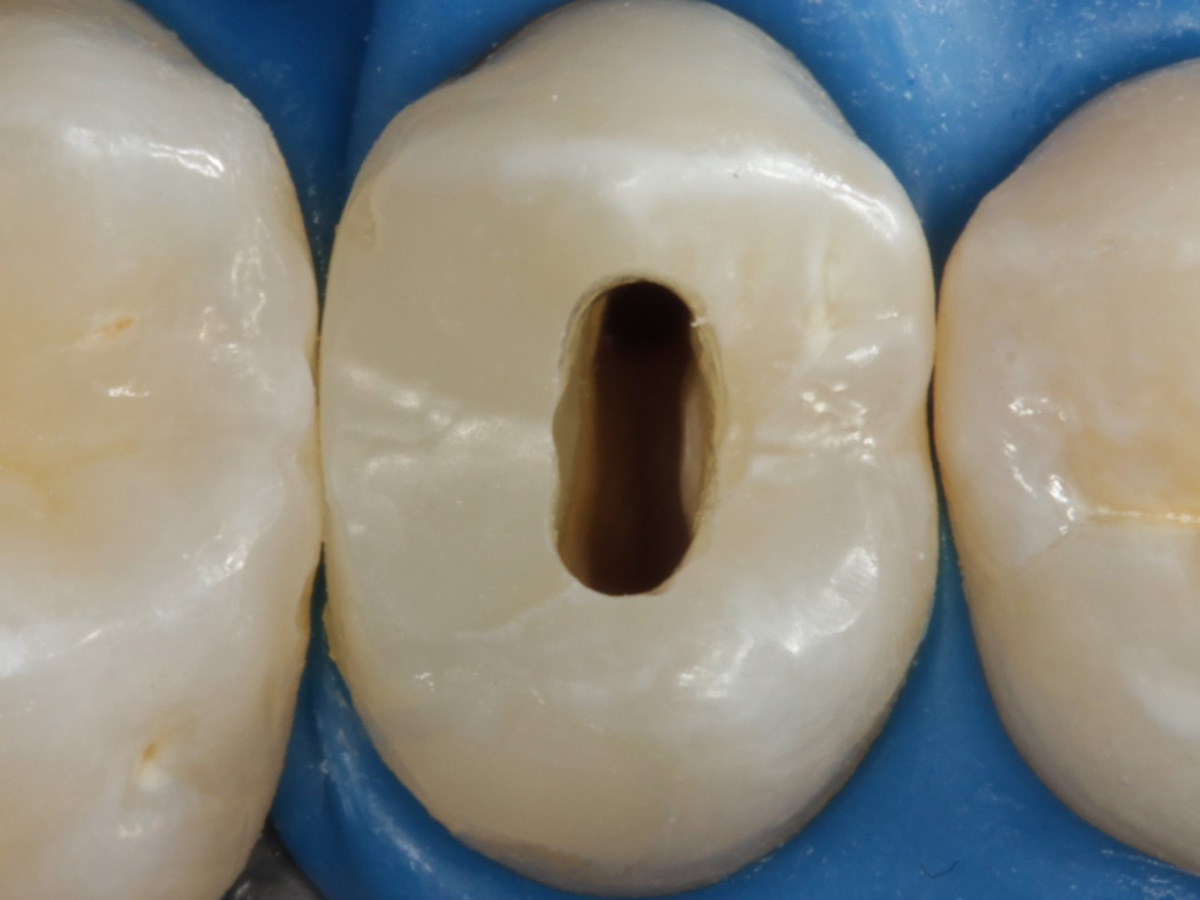

Abbildung 24

Folgesitzung: Trepanation Zahn 25